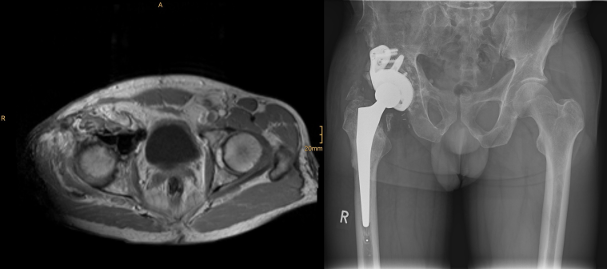

Abbildung 1 [Fig. 1]

Abbildung 1: Präoperative MRT und die implantierte modulare Revisions-Hüft-TEP

Ergebnisse: Der initial als Chondroblastom diagnostizierte Tumor des rechten Acetabulums wurde 1994 erstmalig reseziert. Im Verlauf erfolgten aufgrund von Rezidiven insgesamt 8 Revisionseingriffe bis 2020. Komplikationen umfassten mehrfache lokale Tumorrezidive, eine Streptokokkensepsis mit Infektion des einliegenden Acetabulumspacers (2022) sowie die Entwicklung einer sekundären Coxarthrose. Die Therapie beinhaltete wiederholte Resektionen mit Knochenzementplastiken, eine temporäre Girdlestone-Situation (2023) und schließlich die Implantation einer modularen Revisionshüft-TEP (2023). Zusätzlich entwickelte sich ein therapiebedürftiges Lymphödem des rechten Beins, welches 2024 mittels lymphovenöser Anastomosen behandelt wurde.